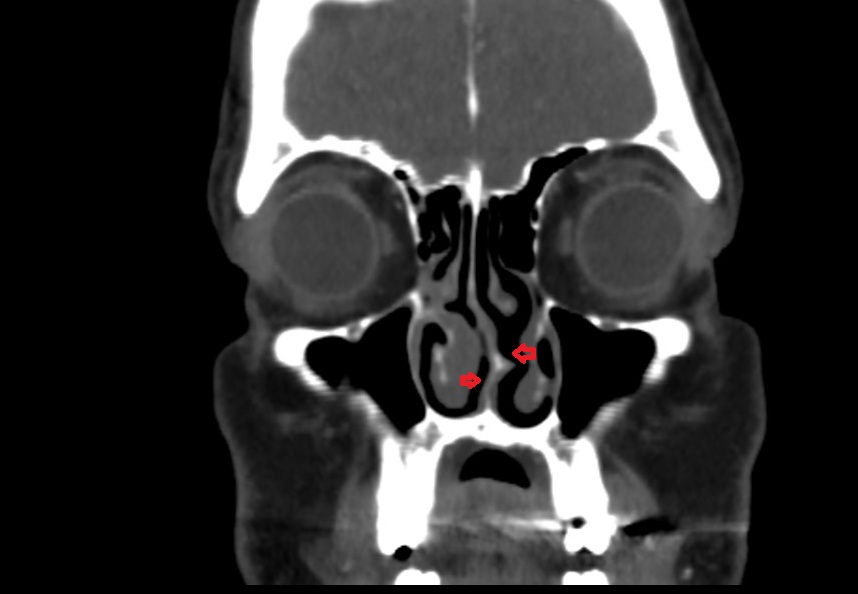

- Inferior nasal concha

- Middle nasal concha

- Nasal septum

- Superior nasal concha